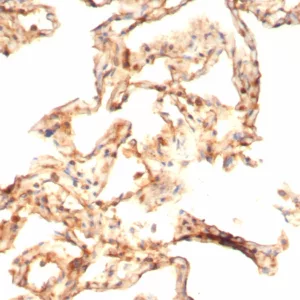

Antibodies against IL-6 are used in research to detect and quantify Interleukin-6 levels in biological samples. Immunohistochemistry, ELISA, and other immunoassays employing anti-IL-6 antibodies help researchers study its role in different diseases and conditions. In a clinical context, IL-6 levels may be measured as part of diagnostic tests to assess the extent of inflammation or to monitor disease activity. Therapeutically, antibodies targeting Interleukin-6 or its receptor (e.g., tocilizumab) are used to treat autoimmune diseases like rheumatoid arthritis and certain inflammatory conditions. Furthermore, these inhibitors are being explored for their potential in managing cytokine storms associated with severe infections, including those seen in some cases of COVID-19.